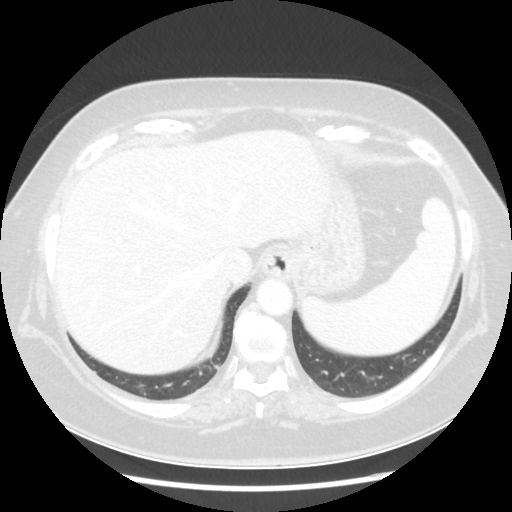

Original VENOUS CT scan

Full window (WL 1023.5, WW 4095 β†’ Low βˆ’1024, High +3071)

Actual HU range: [-1024.0, 1086.0]

Lung window (WL -600, WW 1500 β†’ Low βˆ’1350, High +150)

Actual HU range: [-1350.0, 150.0]

Mediastinum window (WL 40, WW 400 β†’ Low βˆ’160, High +240)

Actual HU range: [-160.0, 240.0]